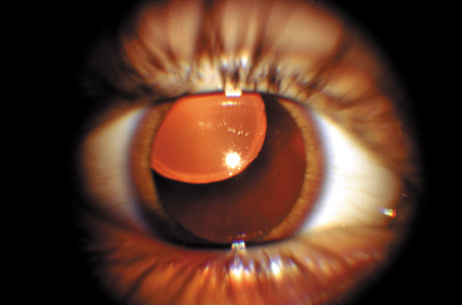

Anterior lenticonus (Figs. 8 and 9) is considered an integral part of AS. The anterior capsule thins and allows the lens to bulge into the anterior chamber, using the pupil as a mold.53 Electron microscopy of the renal glomeruli and anterior lens capsule can confirm capsular thinning and dehiscences.54,55 Anterior lenticonus is typically diagnosed in the second and third decades of life, when it causes clinically significant decreased vision,56 but it may be present in adolescence and result in spontaneous rupture of the anterior lens capsule.57 Posterior subcapsular cataract occurs quite frequently; however, many patients receive glucocorticosteroids for their renal condition, which may play an etiologic role in these cataracts. Additional ocular features described in XLAS include other corneal dystrophies, microcornea, corneal arcus, iris atrophy, posterior lenticonus, spontaneous lens rupture, spherophakia, a poor macular reflex, fluorescein angiogram hyperfluorescence, electrooculogram and ERG abnormalities, and retinal pigmentation abnormalities.58

Fig. 9. AS. Oil-droplet appearance of anterior lenticonus in retroillumination. (Courtesy of Dr. N. Meadow, Manhattan Eye and Ear Hospital, New York, New York.)